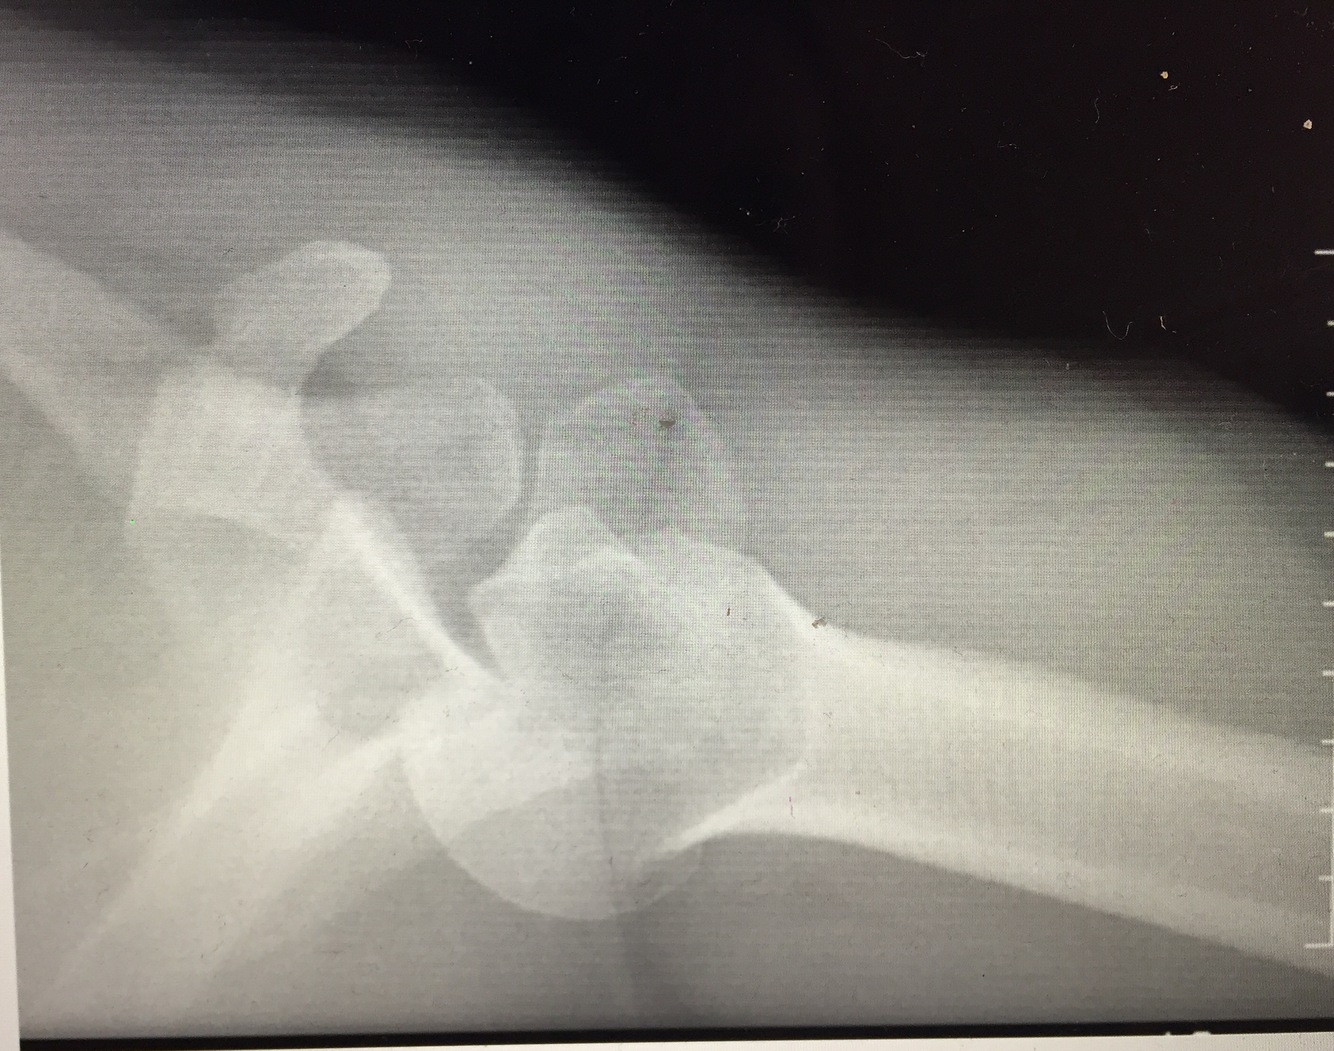

Anterior shoulder dyslocation

Most common form of shoulder dyslocation

Caused by a direct blow or fall on an outstretched arm.

Patient holds the arm slightly abducted and externally rotated.